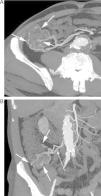

Paciente intervenido de neoplasia esofágica y reconstrucción mediante coloplastia, que presenta hematemesis. A) Reconstrucción coronal de TC que muestra un pseudoaneurisma (flecha gruesa) adyacente a la sonda de alimentación (flecha fina). B) La reconstrucción «volume rendering» demuestra el pseudoaneurisma (flecha gruesa) dependiente de una rama de la arteria cólica media (flechas finas). C) La arteriografía guiada por los hallazgos de la TC confirma la existencia del pseudoaneurisma (flecha), con posterior embolización del mismo.

Paciente con anemia ferropénica y estudios endoscópicos previos negativos, que acude por HDB visible. A) La TC muestra extravasación de contraste en un divertículo de yeyuno (flecha). B) Reconstrucción coronal que muestra el divertículo sangrante (flecha gruesa), con extravasación de contraste a la luz intestinal (flechas finas). C) Reconstrucción «volume rendering» que muestra el aporte vascular al divertículo a través de una rama yeyunal (flechas) de la arteria mesentérica superior.